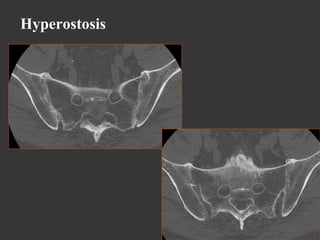

Hyperostosis

•  Diffuse Idiopathic Skeletal Hyperostosis like

Hyperostosis and calcification of tendons and ligaments

Bone bridges along the anterior longitudinal ligament (6

vertebrae at least)

*J. DiGiovanna et al., Isotretinoin effects on bone